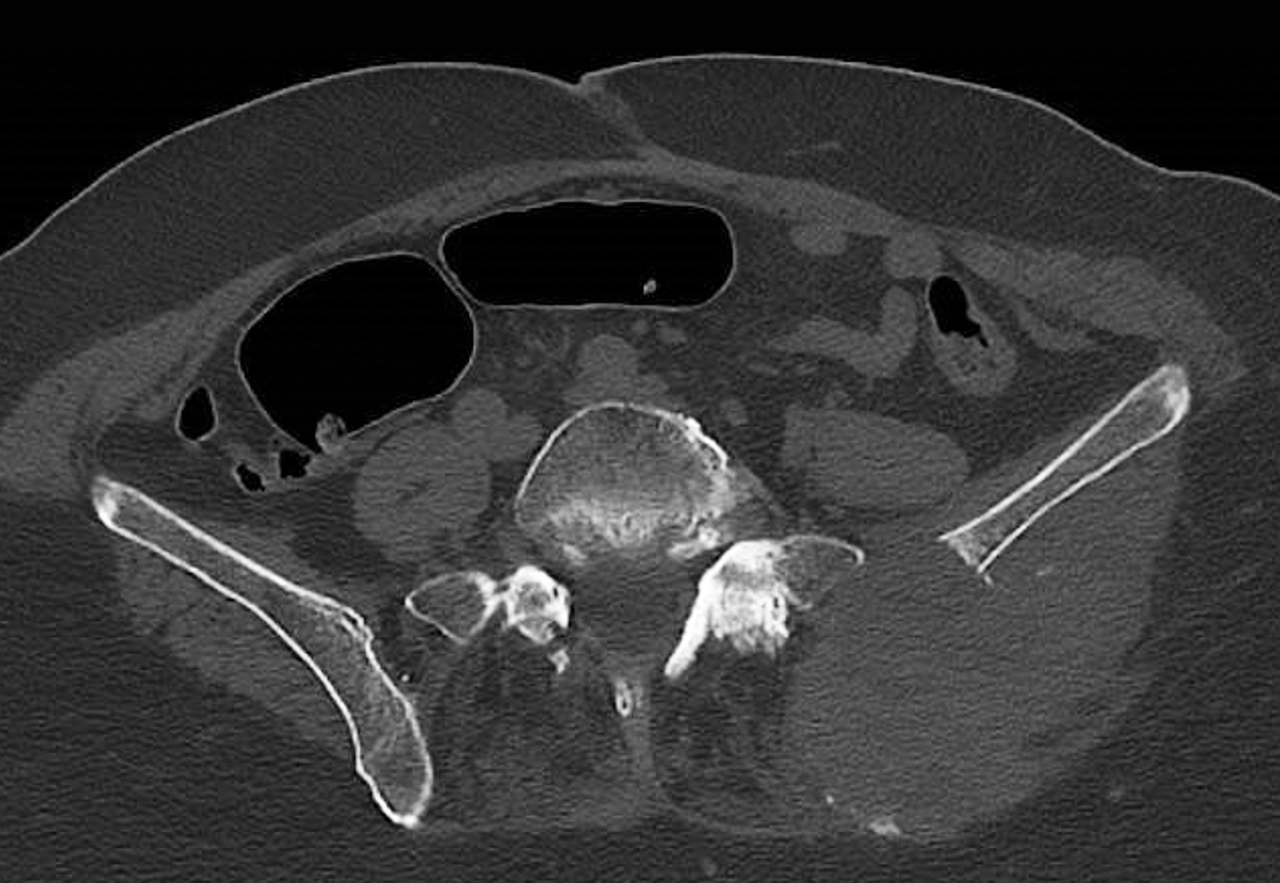

Une femme de 83 ans se plaint de douleurs au niveau de la fesse gauche et d’une impotence fonctionnelle à la suite d’une chute.

Elle a un antécédent de carcinome rénal opéré deux ans auparavant. La calcémie est à 4,13 mmol/L.

Quel est votre diagnostic ?

Devant une métastase osseuse, il faut rechercher un cancer « ostéophile » : rein, sein, thyroïde, prostate, poumon.

L’hypercalcémie survenant au cours d’un cancer du rein peut être liée aux métastases osseuses ou d’origine paranéoplasique.